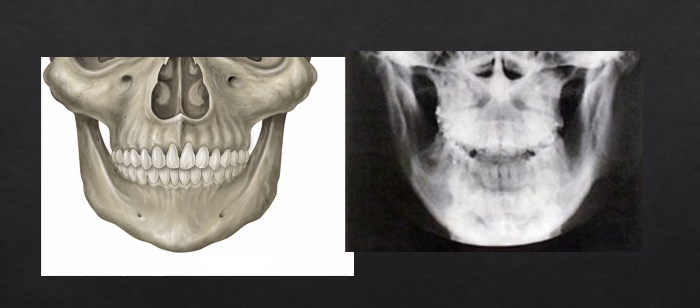

image would form something like this - this is a PA → posterior anterior mandible is

PA radiographs vs panoramic radiographs DPT

the panoramic radiograph looks different because the specialized technique